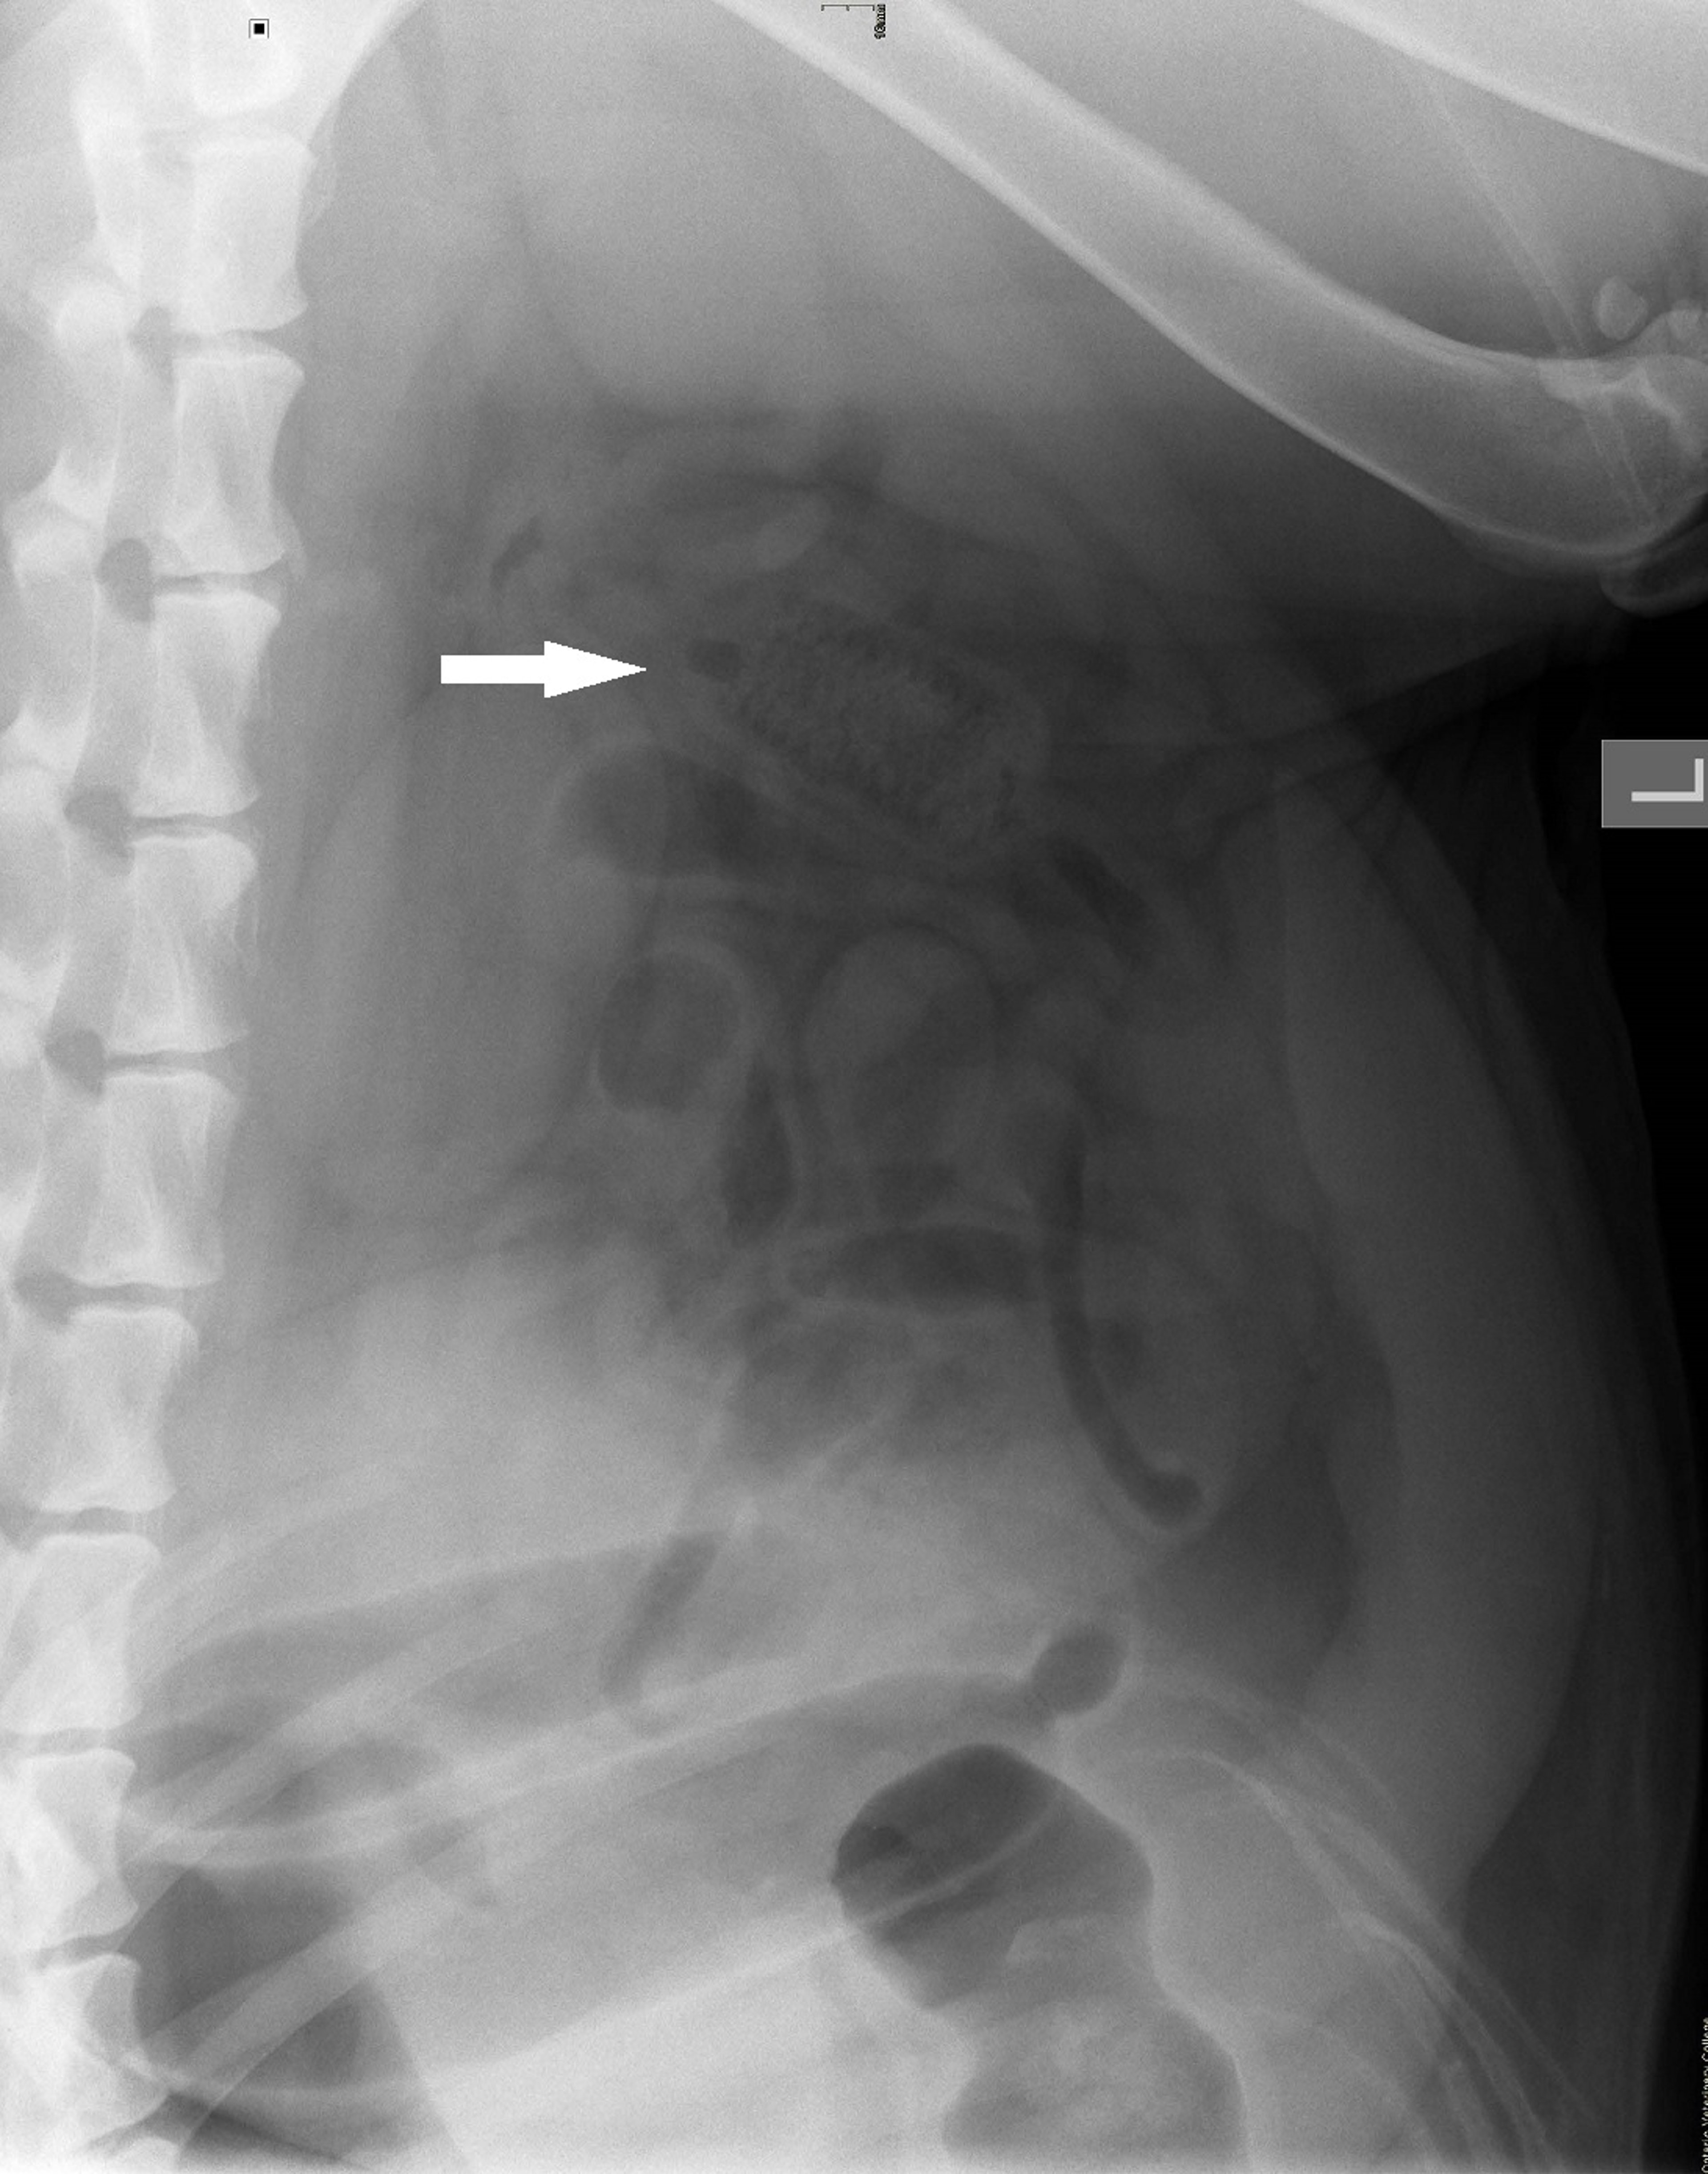

Intestinal obstruction, lateral view, dog

Lateral abdominal radiograph of a two-year-old Labrador Retriever with a corncob small intestinal obstruction.